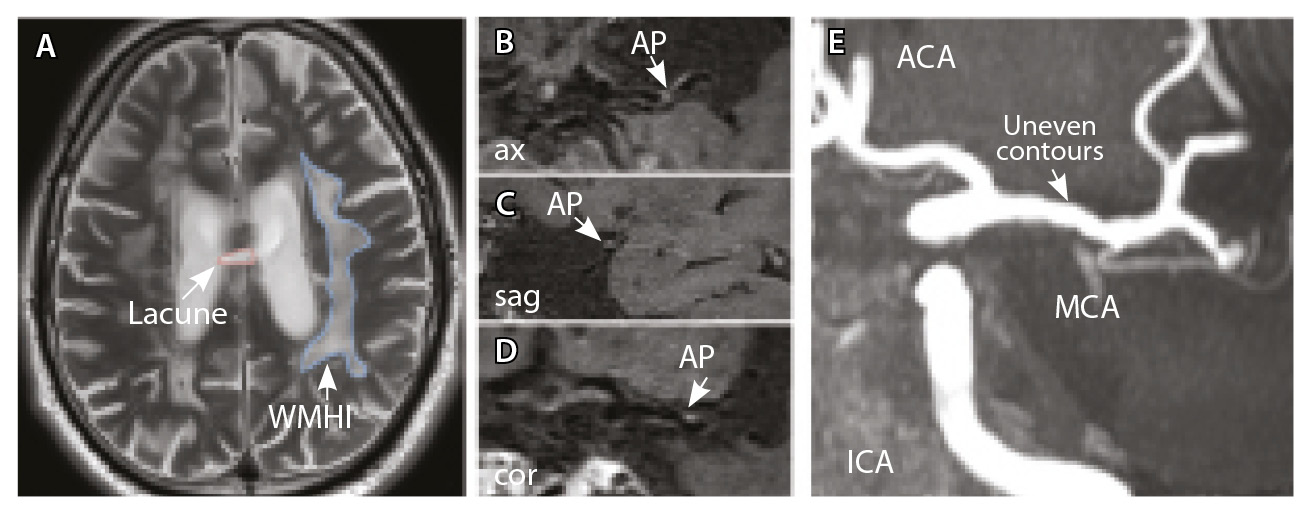

Рис. 3. Пациент Ц., 53 года, с признаками церебральной микроангиопатии (F3 по шкале Fazekas), атеросклерозом интракраниальных артерий, без формирования гемодинамически значимых стенозов. А – магнитно-резонансная томография (МРТ) головного мозга, режим Т2-взвешенного изображения: видны обширные сливные зоны гиперинтенсивности белого вещества (ГИБВ) с наличием на этом фоне лакунарных инфарктов; Б, В, Г – МРТ сосудистой стенки, режим T1-TSE-db-FS после контрастного усиления: в сегменте М1 левой средней мозговой артерии (СМА) визуализируется эксцентричная атеросклеротическая бляшка (АСБ), интенсивно накапливающая контрастный препарат; Д – трехмерная магнитно-резонансная времяпролетная (3D ToF) ангиография: выявляется неровность контуров левой СМА в сегменте М1; ax – аксиальная, sag – сагиттальная, cor – коронарная плоскости; ВСА – внутренняя сонная артерия; ПМА – передняя мозговая артерия

Рис. 4. Пациент К., 69 лет, с признаками церебральной микроангиопатии (F2 по шкале Fazekas) и атеросклерозом интракраниальных артерий, с формированием гемодинамически значимого стеноза в сегменте М1 правой средней мозговой артерии (СМА): А – магнитно-резонансная томография (МРТ), режим Т2-взвешенного изображения: видны множественные сливные очаги гиперинтенсивности белого вещества (ГИБВ); Б, В – МРТ сосудистой стенки, режим T1-TSE-db-FS после контрастного усиления: в сегменте М1 правой СМА визуализируется эксцентричная атеросклеротическая бляшка (АСБ), интенсивно накапливающая контрастный препарат; Г – трехмерная магнитно-резонансная времяпролетная (3D ToF) ангиография: виден стеноз правой СМА в сегменте М1; Д – режим HR Т2-TSE: видна АСБ в сегменте М1 правой СМА; ax – аксиальная, sag – сагиттальная плоскости; ЗМА – задняя мозговая артерия; ПМА – передняя мозговая артерия